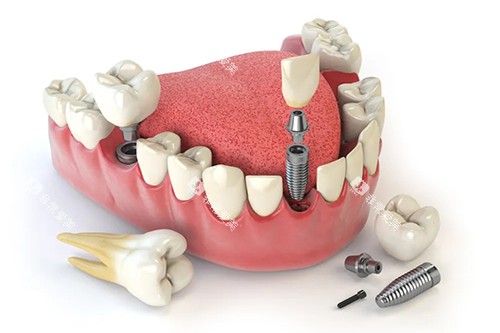

在种植牙方面,医院采用德国卡瓦智能化导航系统,支持即刻种植、ALL - ON - 4/6全口修复,误差控制在0.1mm,单颗种植周期缩短至1小时,大大提高了种植效率和精密度。

在种植牙方面,智能化导板种植技术提升了种植精度,减少了手术创伤,多位患者提到种植后咬合功能修复快,全瓷牙冠修复成效自然。